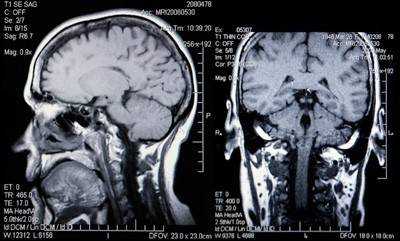

Результаты МР-сканирования на аппарате мощностью 1,5 Тл